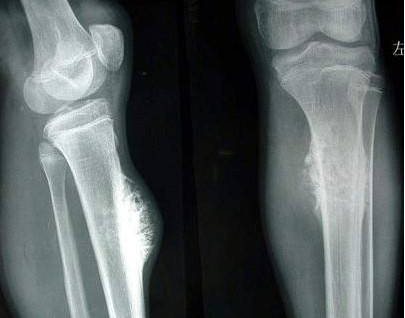

骨癌是发生在骨骼以及附属组织的恶性肿瘤,侵犯性强且容易出现转移,一般早期骨癌患者带有局限性,癌细胞未出现转移和扩散,及时采取根治性手术切除,必要时候术后可进行一段时间的放疗、化疗,治愈可能性还是比较高的。

骨癌能治愈吗骨癌早期有较大几率能治愈,中晚期患者则难度较大,治疗目的主要是延长生存周期。对于比较小的骨癌,临床上多选择根治性切除,如果比较大,可考虑先行化疗和放疗,再进行手术,降低复发,尽可能保证患儿患肢功能。